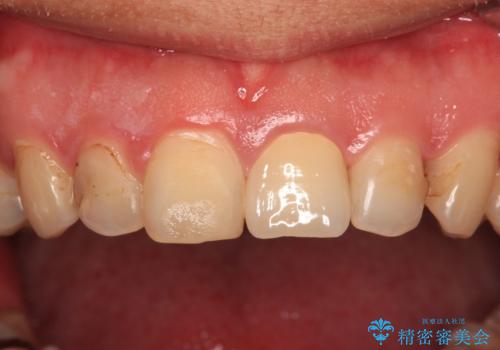

つぎはぎだらけの前歯をオールセラミッククラウンで自然な前歯に

膿の出口も認められたため、まずは根管治療を実施し、オールセラミッククラウンにて補綴治療を行うこととしました。

汚れがつきやすい状態のため、今後も継続してクリーニングを行っていく必要があります。